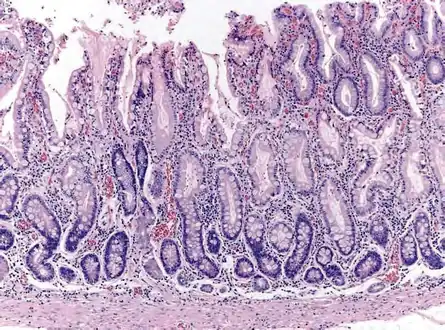

Histopathology of fundic mucosa with atrophy. H&E 10x; square 20x. Fundic-corporal gastric mucosa with extensive loss of gastric glands, partially replaced by pseudo-pyloric metaplasia.